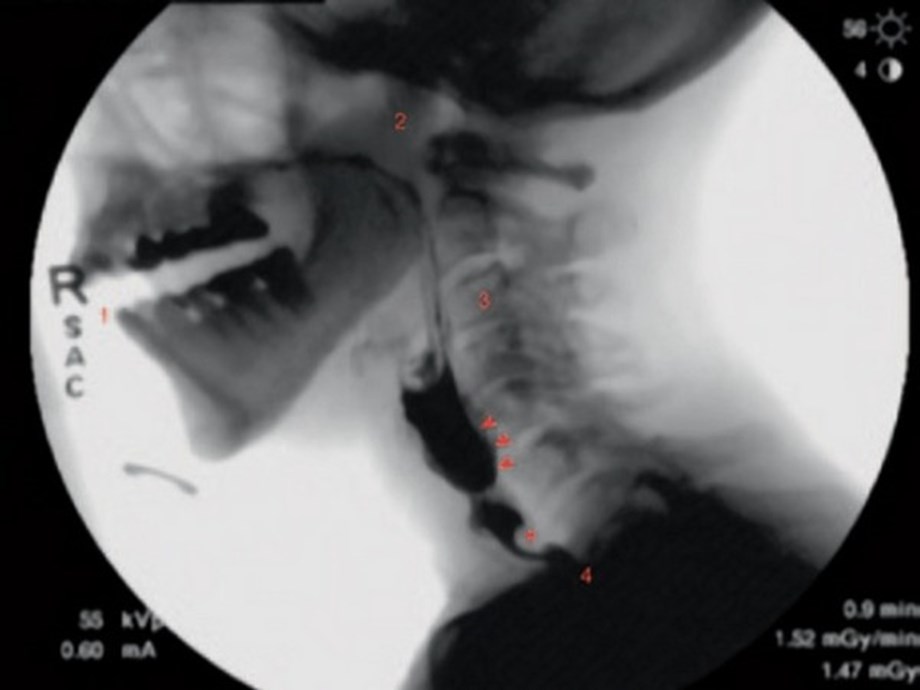

Hence then, the article about research shows new guidelines set to standardize swallowing fluoroscopy was published today ( ) and is available on Devdiscourse ( Middle East ) The editorial team at PressBee has edited and verified it, and it may have been modified, fully republished, or quoted. You can read and follow the updates of this news or article from its original source.